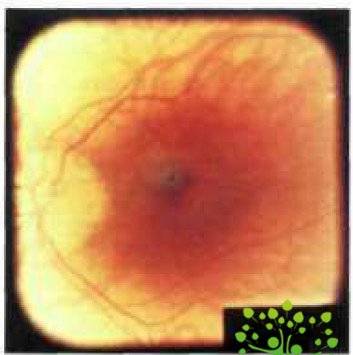

Дистрофические изменения на глазном дне при осложненной близорукости могут локализоваться как в его центральных отделах, так и на периферии. Центральные изменения касаются диска зрительного нерва (ДЗН) и макулярной области. Изменения ДЗН — это формирование миопического конуса, наклонное положение диска и супертракция оболочек (рис.1).

Рис. 1. Глазное дно при неосложненной миопии слабой степени. Мистический конус у височного края диска зрительного нерва (www.glazmed.ru)

Конус — одно из наиболее часто встречающихся клинических проявлений миопии. Он формируется в результате ретракции комплекса стекловидной пластинки (пигментный эпителий — стекловидная пластинка — хориокапиллярис) от края диска зрительного нерва. В результате возникает концентрическая область, в которой белая склера хорошо просматривается через прозрачную нейросенсорную сетчатку. С противоположной стороны диска часто обнаруживается утолщенный край оболочек, покрывающий часть оптического отверстия и называемый супертракцией. Наиболее часто конус располагается с височной стороны ДЗН, но может иметь и любую другую локализацию. По мере прогрессирования миопии размеры конуса увеличиваются, нередко формируются круговые конусы.

С возрастом у больных с высокой прогрессирующей близорукостью развивается перипапиллярная атрофия хороидеи с вовлечением в нее края конуса, который при этом становится неровным. Возникает как бы двойной конус: внутренний склеральный и наружный хороидальный, что является признаком активного растяжения склеры, прогрессирования миопии и, возможно, начала формирования стафиломы. Об этом же свидетельствуют наклонное положение ДЗН (в сторону формирующейся стафиломы) и супертракция оболочек с противоположной стороны. У части взрослых пациентов с высокой прогрессирующей близорукостью развивается частичная атрофия ДЗН, предположительно сосудистого генеза, с соответствующим его побледнением. Изменяется также ход сосудов ДЗН (в виде лежачей буквы «Т» или «У») и уменьшается их калибр.[8]